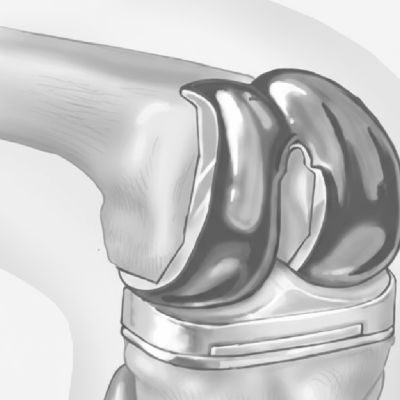

Implante que se coloca en la estructura dañada y sustituye su función, permitiendo al paciente volver a mover la articulación, eliminando el dolor y permitiendo realizar actividad física.

Implante que se coloca en la estructura

dañada y sustituye su función, permitiendo al

paciente volver a mover la articulación,

eliminando el dolor y permitiendo realizar

actividad física.

Sustitución de la articulación desgastada por

una pieza sintética para recuperar la función

Implante que se coloca en porción dañada de la rodilla. Este procedimiento reduce riesgos, sangrado y permite realizar deportes en pacientes jóvenes con desgaste.